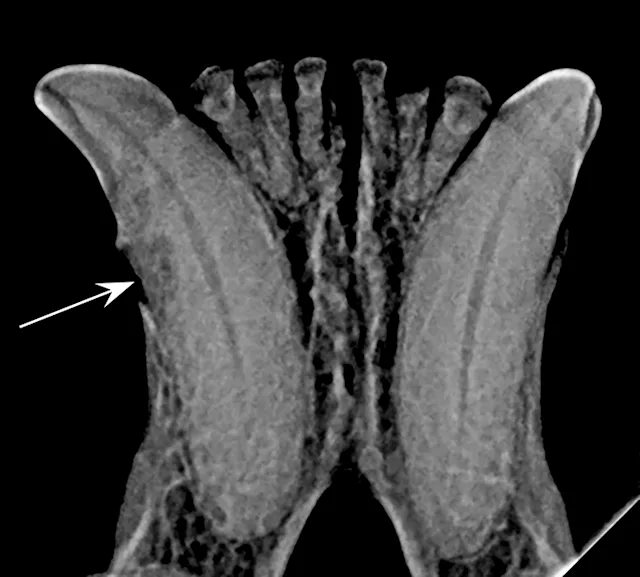

FIGURE 1: Periapical lucency

Periapical lucency develops secondary to bone loss around the tooth root caused by endodontic, neoplastic, or periodontal disease. In this dog, periapical lucency of the maxillary first and second molars (red arrows) developed secondary to periodontal disease. Periapical lucency secondary to endodontic disease (caused by exposure of the pulp from a slab fracture [blue arrow]) is also present surrounding the roots of the right maxillary fourth premolar (white arrow).

Observation of marked mobility of the molars would be expected on anesthetized examination. In this dog, the maxillary fourth premolar would likely not be mobile, as there is still bone surrounding the root apices. Extraction of the maxillary fourth premolar and first and second molars is indicated.